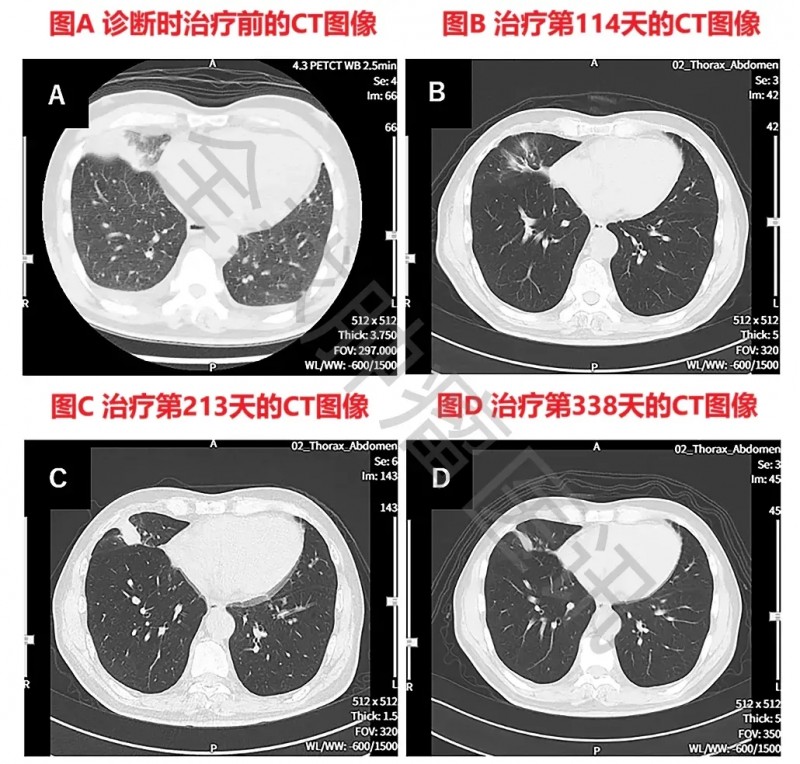

治疗成效十分显著:患者无进展生存期(PFS)超577天,期间体能状态良好,可正常生活。其癌胚抗原(CEA)曾一度持续上升,后续经雷莫芦单抗+多西他赛联合治疗后降至5.9。影像检查显示,治疗前PET-CT提示全身广泛转移;治疗第479天复查时,仅右肺(直径1.0cm)及肝脏(直径1.7cm)残留两处转移灶,其余病灶均明显改善。此外,胸部CT结果显示,治疗第114天肺部原发病灶已近乎消失;第213天虽出现局部复发,但第338天时,原发及复发病灶均显著缩小。

▼该患者WT1-DC治疗前后胸部CT图像对比

▲图源“Cureus”,版权归原作者所有,如无意中侵犯了知识产权,请联系我们删除